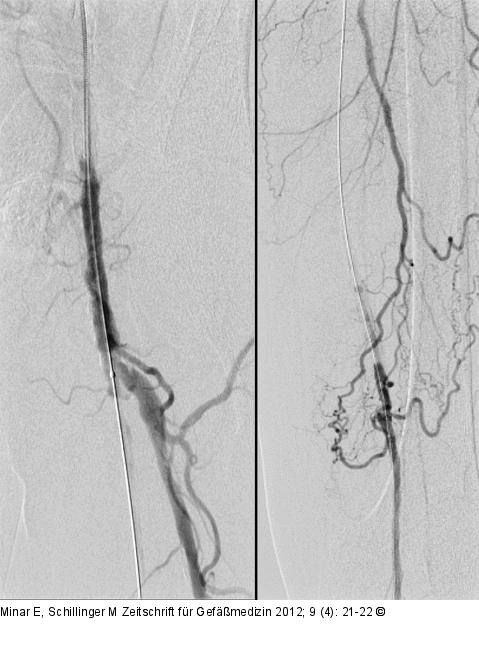

Abbildung 2: Reentry Nach Passage mit dem Führungsdraht und Ballonkatheter. |

Abbildung 2: Reentry

Nach Passage mit dem Führungsdraht und Ballonkatheter. |